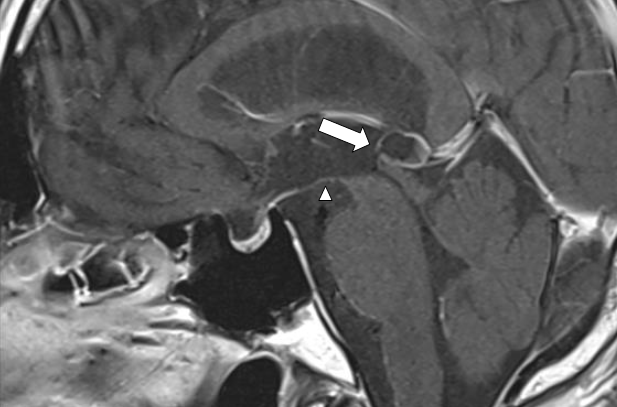

Figure 2 On magnetic resonance imaging, the cyst's signal inside the cyst was stronger than that of the CSF fluid and less strong than the surrounding brain parenchyma and higher than that of the cerebrospinal fluid.

Figure 5 Postoperative magnetic resonance imaging showed the perforated area of the cyst (arrow), and third ventricle (arrowhead).